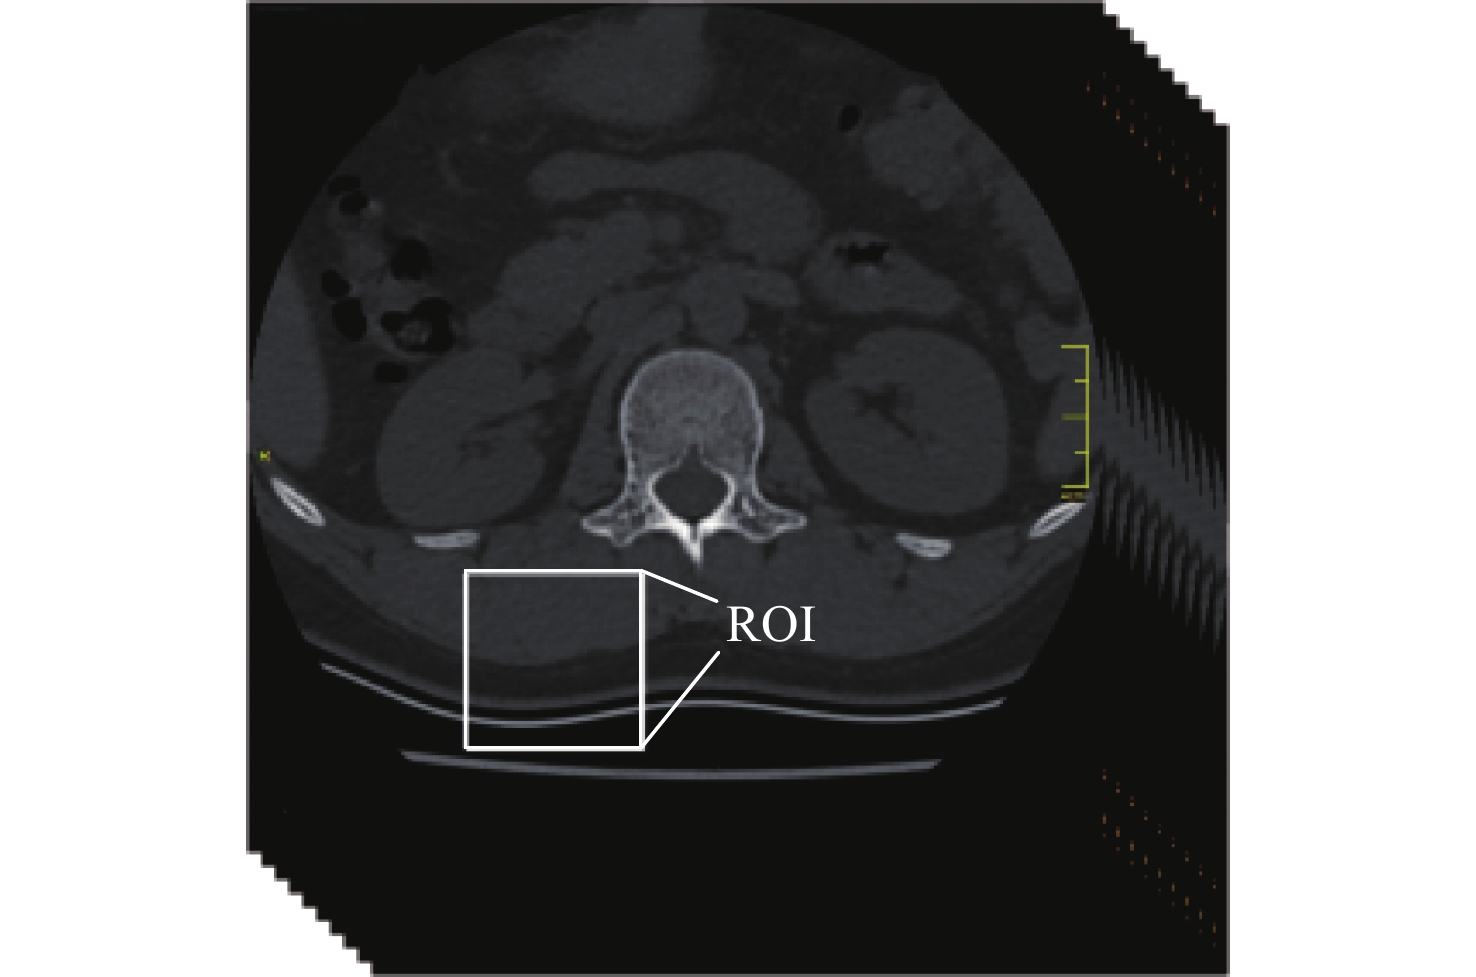

• In an attempt to accurately analyze high load, the finite element model established by clinical CT data was unable to capture the fine geometric features and heterogeneous properties of vertebrae, leading to an inaccurate analysis of the high rate of thoracolumbar spine injuries on fighter pilots during ejection. A finite element model of the thoracolumbar spine (T12-L2) was constructed based on nonlinear finite element, which represents the cortical thickness, cortical density, and cancellous bone density of specific-objects, to analyze the biomechanics of high load on the thoracolumbar spines of pilots during ejection. The object-specific finite element model was constructed based on the CT data of the thoracolumbar spine, and the cortical bone thickness and density values obtained from cortical bone mapping (CBM) were incorporated into the CT-based finite element modeling process of the thoracolumbar spine, and the elastic modulus of each element was calculated according to the Hounsfield units (HU) value to realize the heterogeneous assignment of material. By using the same loads and boundary conditions as those found in published in vitro studies, the model's correctness was confirmed. A Additionally, a simulation and computation were made of the biomechanical reaction of the thoracolumbar spine brought on by the ejection load in the upright, flexion, and extension physiological motion situations. The results showed that the vertebral load transfer characteristics were significantly different among the three different physiological motion conditions subjected to ejection loading, with the upright physiological motion conditions resulting in the least amount of direct acute injury to the vertebrae from the high load.